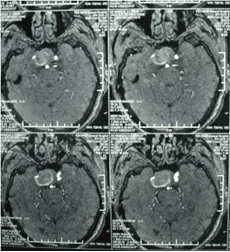

顱內動脈瘤是指腦動脈的局部性異常擴大,多在腦底動脈的分叉處或分支的夾角向外突出,多呈囊狀。TCD對顱內動脈瘤的總檢出率為67 %,動脈瘤>1cm的檢出率為82 %。TC D 對較大動脈瘤的檢測有其特征性表現,其典型表現為:瘤體內血流速度明顯低于載瘤動脈血流速度,其收縮峰陡峭或多峰不整,舒張期末流速極低或斷流,PI 值增高,多為雙向血流,聲頻低鈍,似撞擊樣轟鳴音。

經顱多普勒

頸內動脈虹吸段巨大動脈瘤(約3cm ×3cm